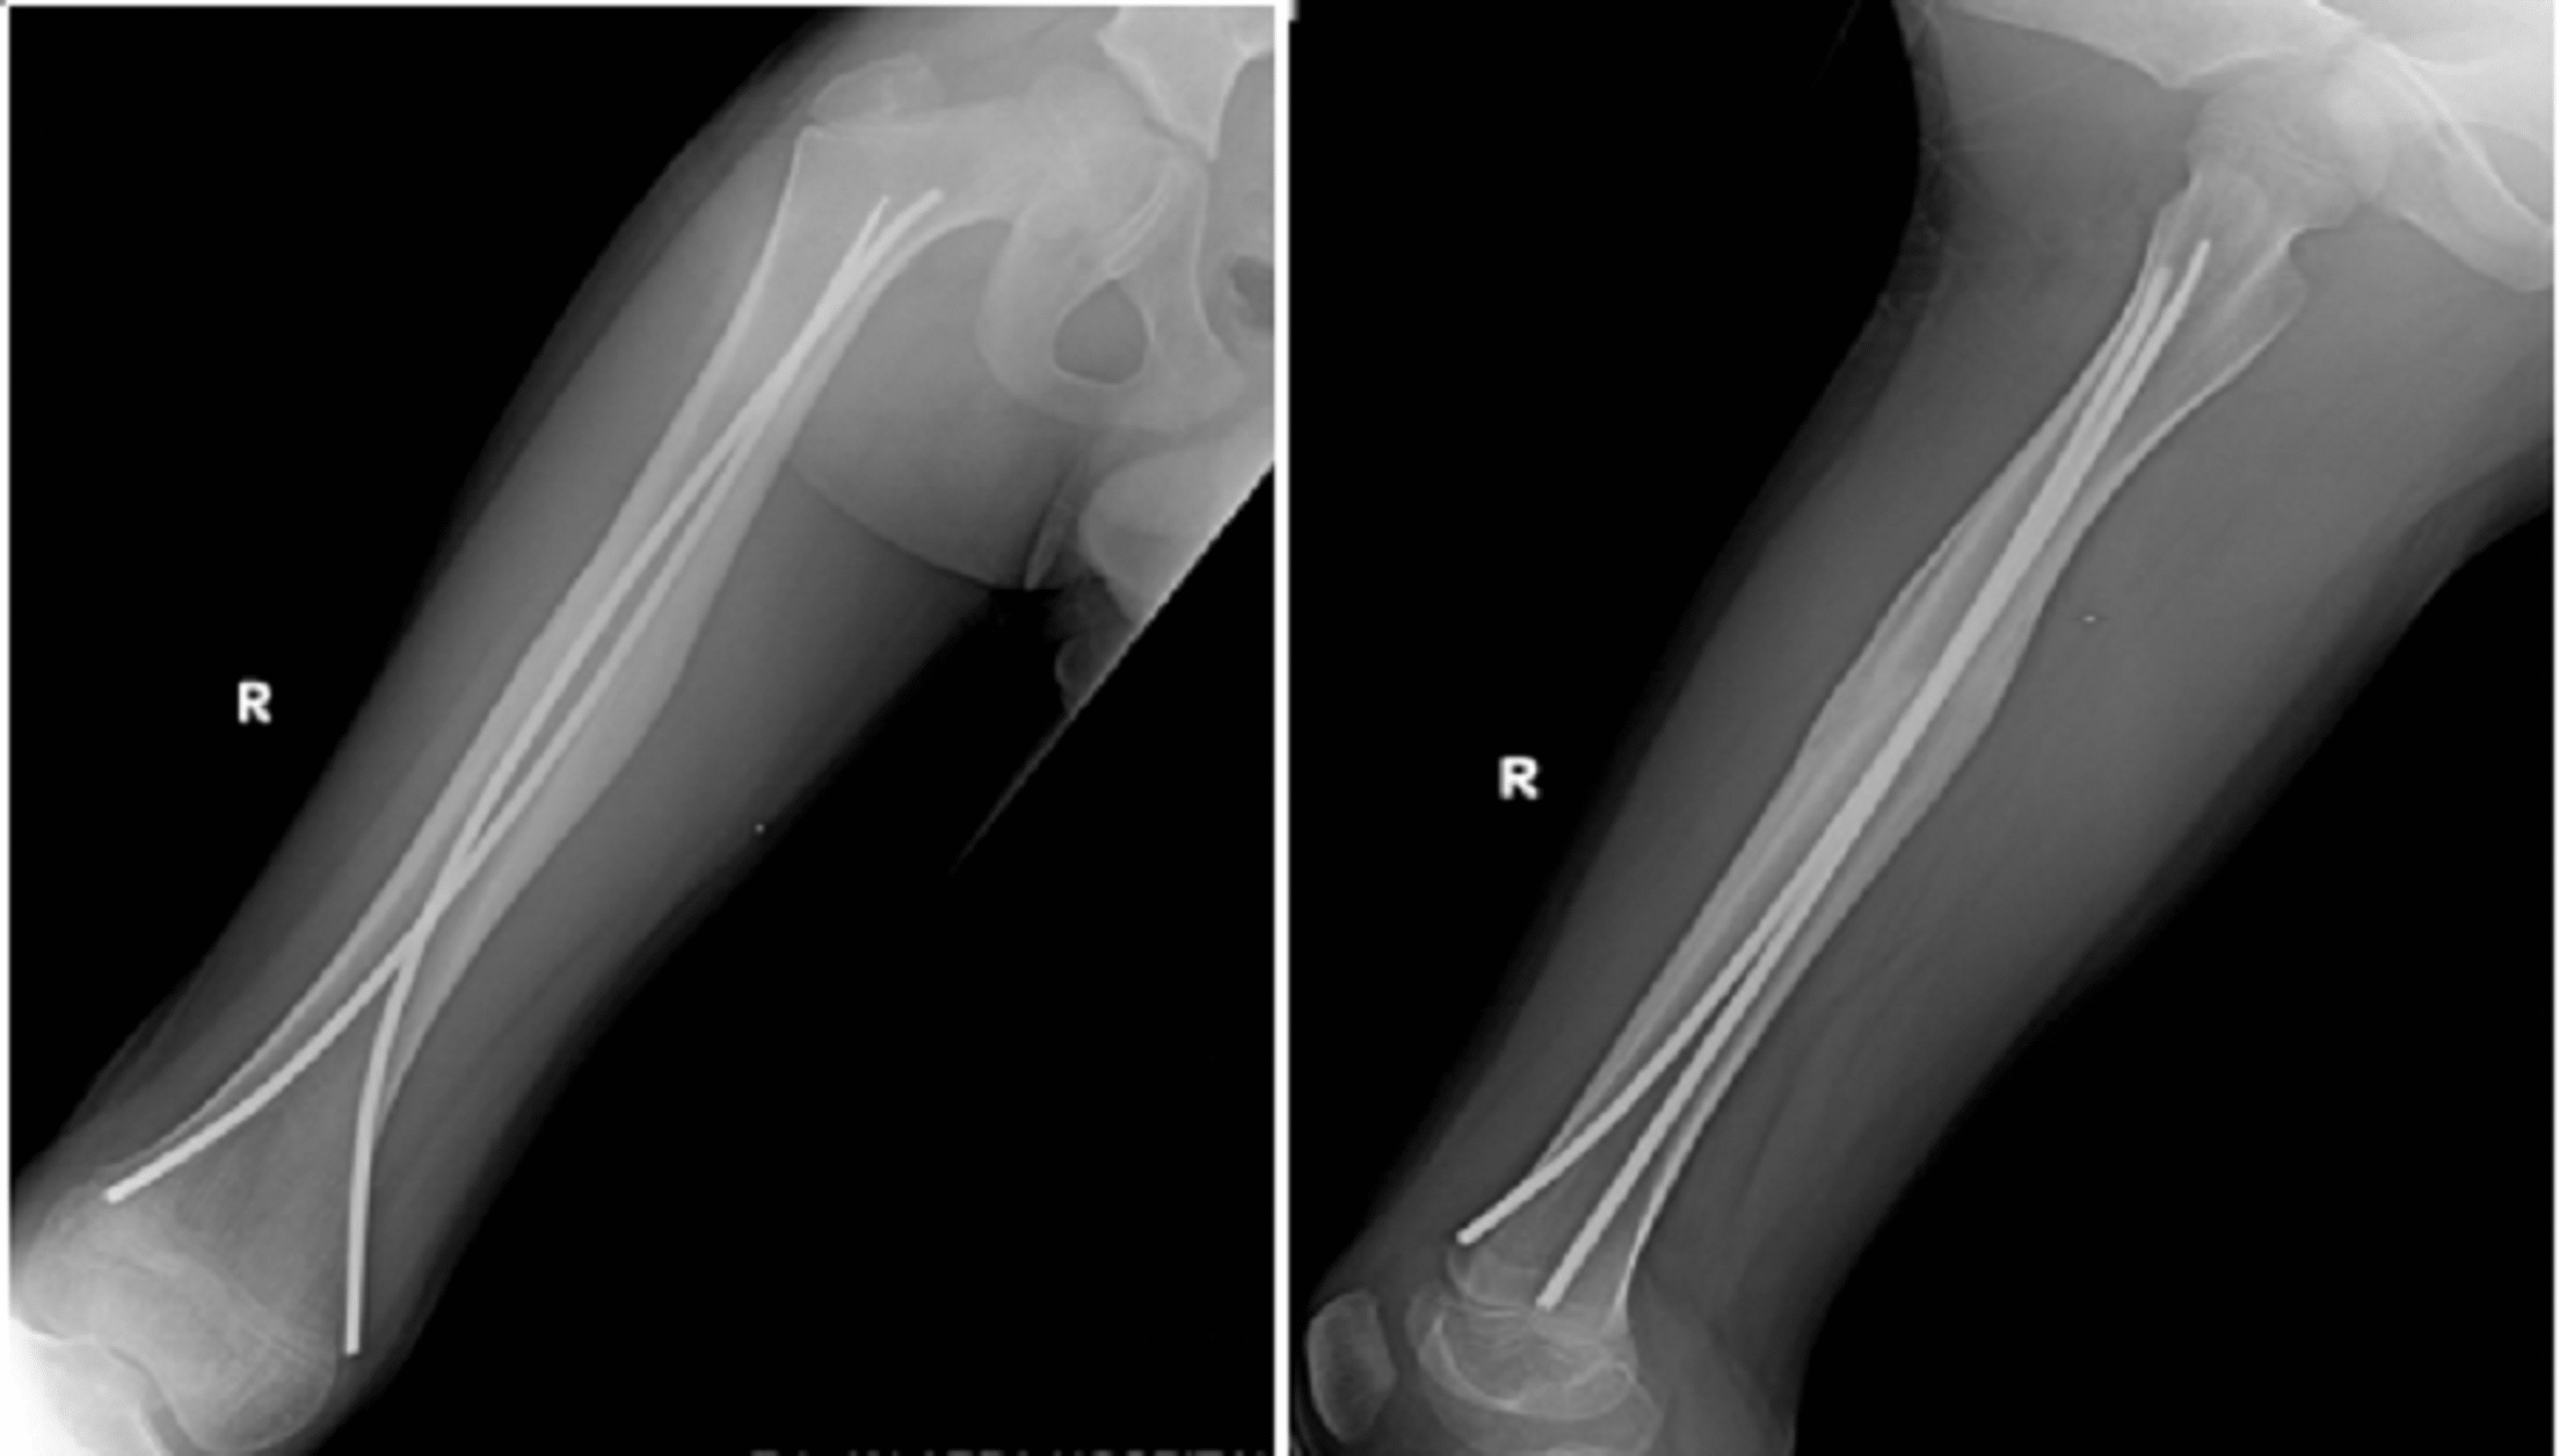

Tibia and femur with elastic rods (Nancy nails) Download Scientific Titanium Rod In Femur Side Effects no statistically significant increase in the titanium level was seen 12 months after surgery (mean difference: unhealed fractures (nonunions): Vehicle accidents are one of the primary causes. on jan 15th i underwent a 7hr op for a fractured femur, tib and fib. Usually, the rod is made of titanium and they come in different lengths and diameters. Titanium Rod In Femur Side Effects.

Cureus Treatment of Diaphyseal Fractures of the Femur in Paediatric Titanium Rod In Femur Side Effects Older adults can fracture their femur from a fall because their bones tend to be weaker. when i was 19 years of age i suffered a gunshot wound which resulted in a fractured femur, a titanium rod was installed in my right. the results of this review support the use of titanium implants in certain clinical fracture scenarios.. Titanium Rod In Femur Side Effects.